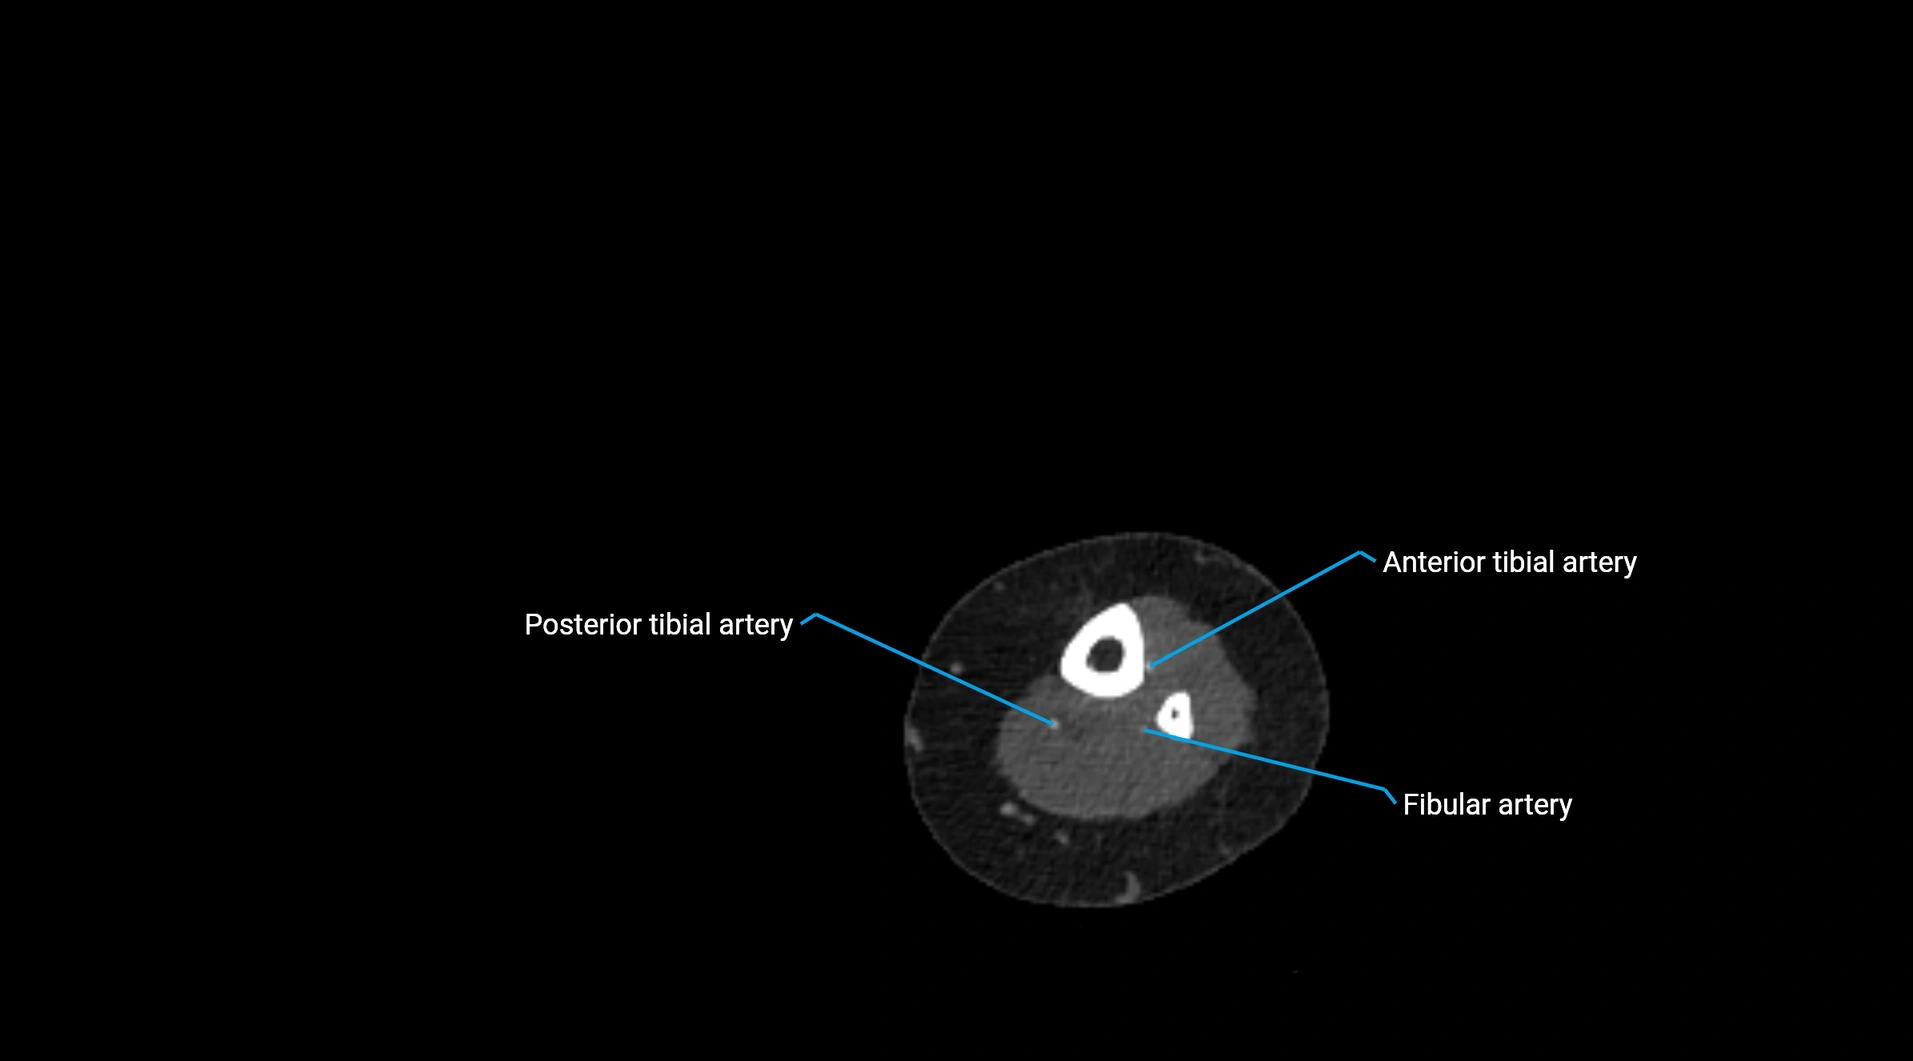

CT Appearance

Non-contrast CT:

• Appears as a tubular soft tissue structure anterior to vertebral bodies

• Calcified atherosclerotic plaques appear as hyperdense foci along the wall

• Useful for screening abdominal aortic aneurysm (AAA) size and mural calcification

Contrast-enhanced CT (CTA):

• Gold standard for abdominal aortic imaging

• Provides excellent detail of lumen, wall, aneurysm, thrombus, and branch vessels

• Multiplanar and 3D reconstructions help in aneurysm measurement, stent graft planning, and dissection evaluation

• Detects acute rupture, traumatic injury, or occlusion with high sensitivity